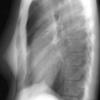

Normal  lateral

24 yo male

Date: 06/08/2016

Views: 5221